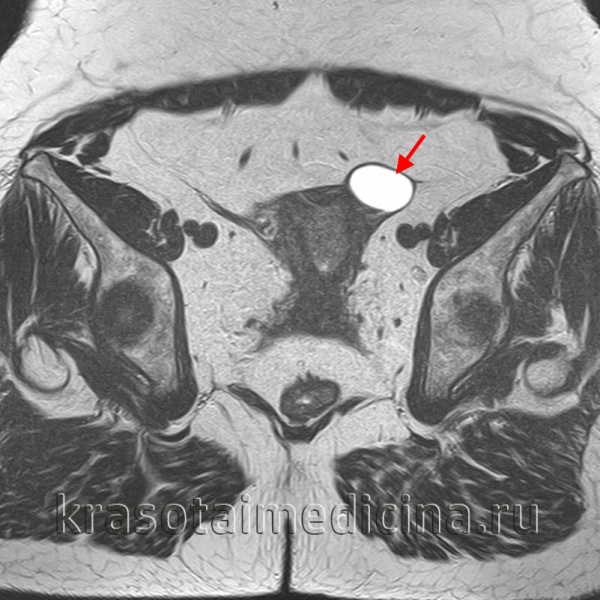

Диагностика начинается с подробного сбора анамнеза с особым вниманием к семейному, так как существует генетическая предрасположенность к развитию цистаденом. Показан осмотр в зеркалах, бимануальное ректовагинальное исследование. Проводится трансвагинальное ультразвуковое исследование, при выявленных больших размерах опухоли оно дополняется трансабдоминальным исследованием. Также возможно выполнение КТ или МРТ органов малого таза в случае подозрения на наличие злокачественного процесса или при малой информативности данных ультразвукового исследования.

В процессе гинекологического УЗИ точно устанавливаются размеры кистомы, толщина капсулы, уточняется наличие камер и сосочковидных разрастаний. При пальпации живота, а также с помощью УЗИ брюшной полости может выявляться асцит. Обнаружение опухоли яичника требует исследования онкомаркера СА-125. В ряде случаев для уточнения диагноза целесообразно проведение КТ или МРТ малого таза. Окончательное подтверждение диагноза и выяснение морфологической формы папиллярной кистомы яичника производится в процессе диагностической лапароскопии, интраоперационного гистологического исследования.

- компьютерной или магнитно-резонансной томографии (КТ или МРТ), дающих сведения о расположении, размерах, структуре, содержимом кисты яичника и ее отношении к предлежащим органам

Для объективного подтверждения наличия кистомы яичника и определения ее размеров выполняется УЗИ органов малого таза, КТ или МРТ-исследование. Характер кистомы яичника уточняется с помощью исследования крови на онкомаркер СА-125, пункции брюшной полости через задний свод влагалища с цитологическим анализом жидкости. По показаниям выполняются биопсия эндометрия, УЗИ молочных желез.

При бимануальном исследовании при достаточно большом размере опухоли можно определить ее величину, локализацию, консистенцию, характер поверхности, подвижность и др. Более информативным методом исследования является УЗИ, которое позволяет четко визуализировать содержимое опухоли, определить ее взаимоотношение с окружающими тканями, дифференцировать новообразование от миомы и других опухолей малого таза.